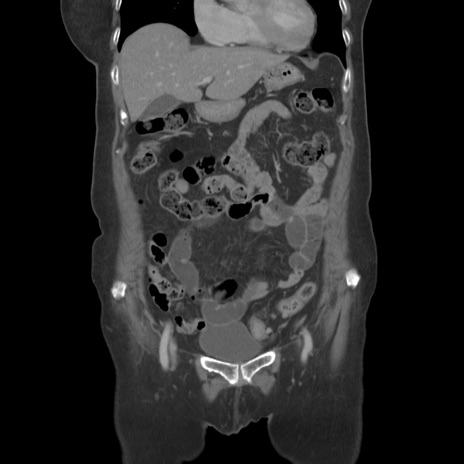

症例19(冠状断像)

【症例】80歳代女性

【主訴】下腹部痛

【現病歴】約8時間前より下腹部痛の出現あり、救急外来受診。

【既往歴】両側付属器切除

【身体所見】意識清明、下腹部正中に手術痕あり、その部位に一致して圧痛と反跳痛あり。腸蠕動音は亢進。

【データ】WBC 9300、CRP 0.15